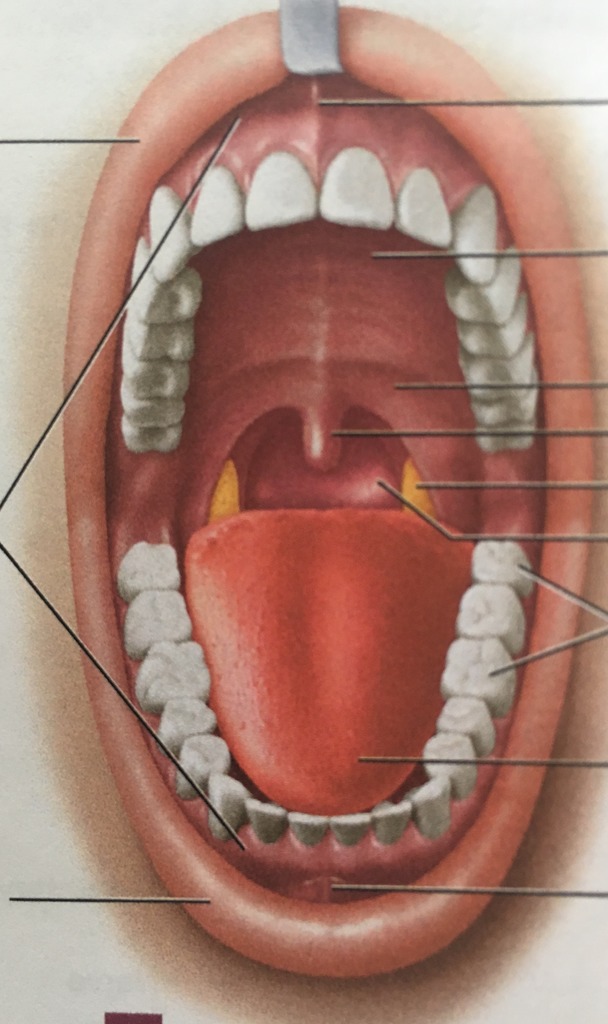

Structures Of The Mouth Diagram Structure Of Oral Cavity. Hu

Mouth teeth tongue gums anatomy diagram parts lips labeled esophagus figure physiology structure pharynx structures ii palate includes 23.3 mouth, pharynx and esophagus: anatomy and physiology (2023) Structure of mouth and oral cavity #1 diagram

Structure of oral cavity. human mouth anatomy stock vector Mouth anatomy britannica oral cavity anterior science Mouth teeth structures

Mouth anatomy dental teeth diagram human label oral hygiene tooth muscles tongue tonsil hygienist smile jaw pharynx inside assistant nameOral cavity anatomy with educational labeled structure vector Oral mucosa anatomyDental palate cavity vestibule britannica assistant anterior hygiene frenulum sublingual gland gums tissue linguae labial submandibular inferior duct incisor molars.

Human mouth anatomy teethHuman mouth diagram Mouth & throat anatomyHuman mouth.

Cavity labeled digestive dental physiology vectormine cavities palateHuman mouth diagram Figure 284a,b: structures of the mouth and teethAnatomy mouth stock illustration google diagram frenectomy lightbox cart tongue adult tie twitter share human depositphotos.

The mouth, pharynx, and esophagusWhat are the 3 key functions of the teeth? Anatomy of the mouthMouth teeth diagram with label.